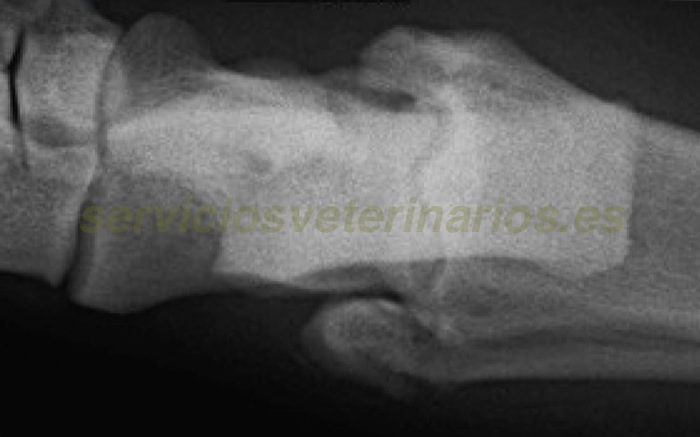

| Pruebas | Se realiza analítica completa con bioquímica y hemograma sin alteraciones. Las radiografías prequirúrgicas se hacen bajo anestesia y no se diagnostica la fractura en la inserción del ligamento en extremo distal del peroné aunque sí se ve una cierta irregularidad en este área. |

Con un gran aumento en la radiografía digital sobre la inserción del colateral lateral (maleolo lateral del peroné en parte inferior de la imagen) se puede ver una irregularidad aunque inicialmente no se diagnosticó como fractura. A pesar de la inflamación de la zona se apreció gran inestabilidad compatible con una lesión del ligamento colateral.